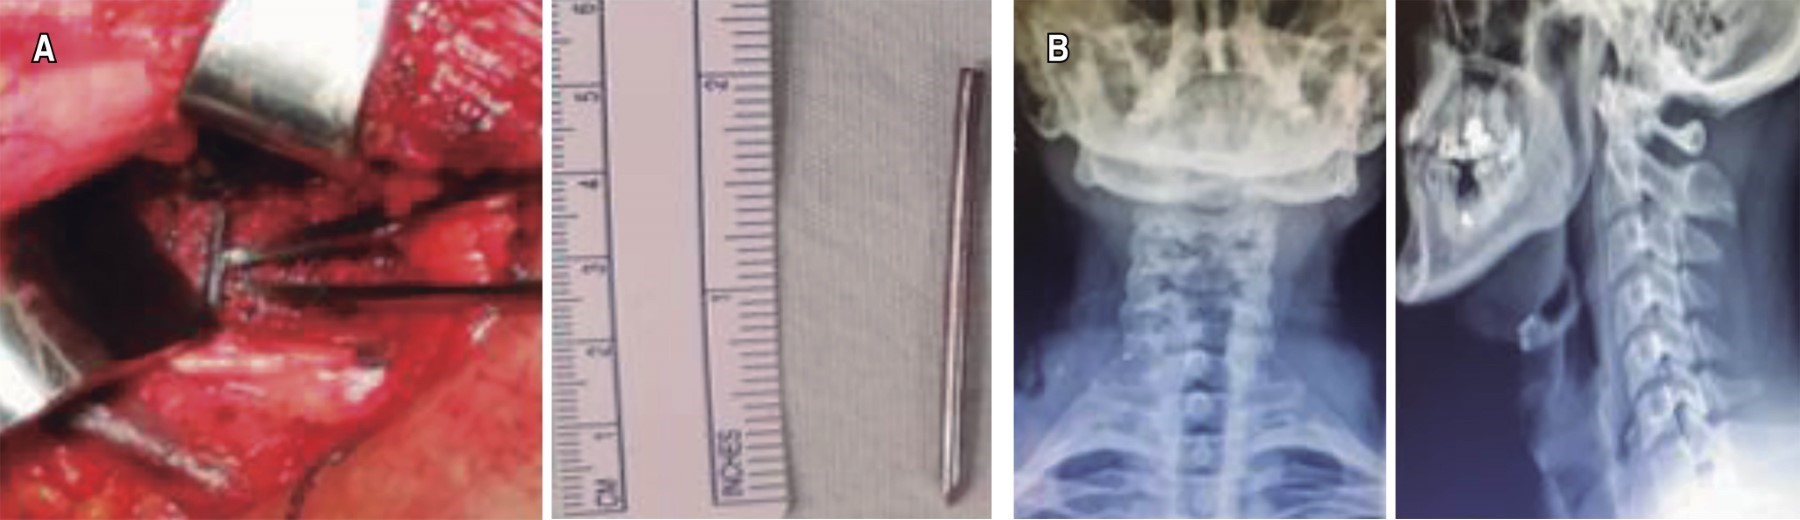

Se efectuó intervención quirúrgica con abordaje cervical anterolateral derecho. Se realizó disección neurovascular y, con ayuda de intensificador de imágenes, en el espacio interapofisario transverso de C7-T1, se localizó el extremo lateral del clavo Kirschner que migró (Figura 4). Se procedió a retirarlo. En el postoperatorio, el paciente presentó parestesias en los dermatomas C5 y C6 y parálisis del bíceps braquial, que se atribuyó a la manipulación del área quirúrgica. Se inició fisioterapia temprana y hubo una recuperación total a los tres meses del postoperatorio.

Paciente masculino de 43 años de edad quien, cinco meses previos a la atención hospitalaria, presenta cervicalgia moderada sin sintomatología acompañante sin recibir atención médica. Siete días previos a la valoración y posterior a trauma contuso en región cervical y dorsal, presenta dolor intenso en región cervical, además de pérdida súbita de sensibilidad y fuerza motriz en cuatro extremidades. El paciente tiene como antecedente osteosíntesis de clavícula derecha con placas de reconstrucción y clavo Kirschner en institución privada hace ocho años. Al momento de la valoración actualmente reportada, se presenta movilizado en silla de ruedas, con tetraparesia, nivel neurológico C6, ASIA B. Se revisan radiografías anteroposterior y lateral de columna cervical en las que se evidencia clavo Kirschner en segmento C7-T1 (Figura 10). En tomografía computarizada se constata invasión de cuerpo extraño a conducto medular (Figura 11). Se realiza extracción quirúrgica de clavo Kirschner mediante abordaje supraclavicular derecho (utilizado para exploración de plexo braquial), se realiza disección neurovascular; se logra identificación directa de punta de clavo K mediante intensificador de imágenes. Se retira el clavo sin dificultad, no presentó fuga de líquido cefalorraquídeo (Figura 12A y B). El paciente en postoperatorio inmediato y a los 45 días posteriores a la cirugía no presenta cambios en estado neurológico.